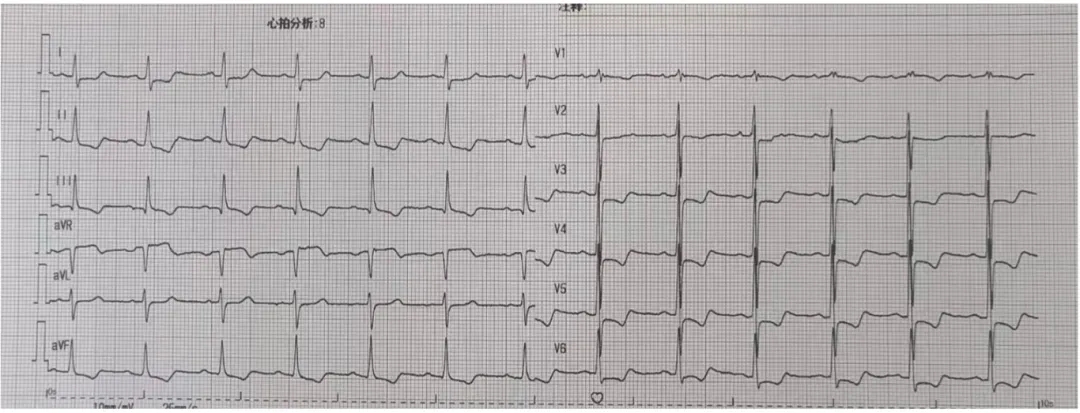

术前讨论:患者77岁老年男性,3年前行TAVR术,此次再发主动脉瓣关闭不全,经评估排除感染,考虑主动脉瓣生物瓣毁损,患者心衰重,消瘦、虚弱,经多学科讨论,TAVR in TAVR手术指征明确,考虑行TAVR in TAVR治疗,术前评估瓣架内径:瓣环26.6,LVOT 26.6,瓣架位于瓣环以下:5(无窦)-13(左窦)mm,左侧冠脉高度12.1,右侧13.4,左冠VTC5.3mm VT-STJ:0mm,右冠VTC4.4mm VT-STJ0mm, 主动脉弓部角度可,存在钙化,双侧髂股动脉内径可,右侧股动脉分叉位于股骨头平面中部 左侧股动脉分叉位于股骨头下缘中部,建议左侧入路,拟植入29号瓣膜,因患者冠脉风险大,需控制瓣膜植入深度,拟控制S3上缘位于启明第3-4个交接点处,同时需关注冠脉(Guidzilla预置保护)。